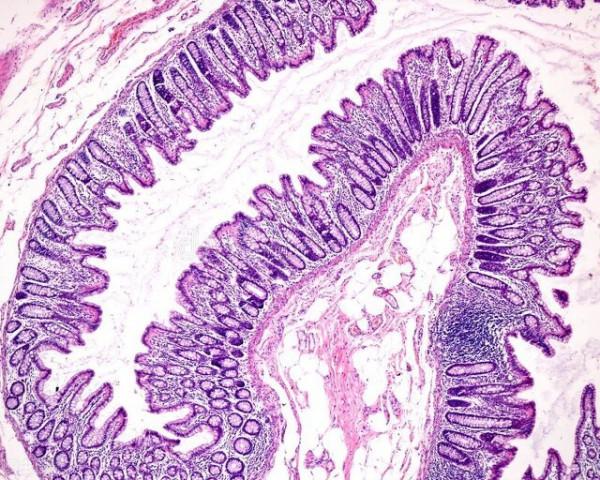

那麼病理科檢查什麼呢?病理科檢查是用顯微鏡再仔細觀察粘膜的微細結構,進一步判斷粘膜的病理變化,提出診斷意見[1]。

對於炎症性腸病來說,粘膜的病理變化多樣,不同患者或同一患者在不同的階段可以表現為不同的病理形態特徵,難以簡單固定的標準化診斷。為此醫學專家們,尤其是病理學專家們多次探討,制定了相關共識意見。

炎症性腸病,粘膜活檢先要觀察粘膜的結構和粘膜固有層炎性細胞是否增多。

指的是腸粘膜結構沒有改變,粘膜固有層細胞無顯著增多的炎性細胞。